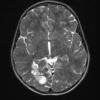

NEOPLASMS (NEURONAL)

DNET (13)